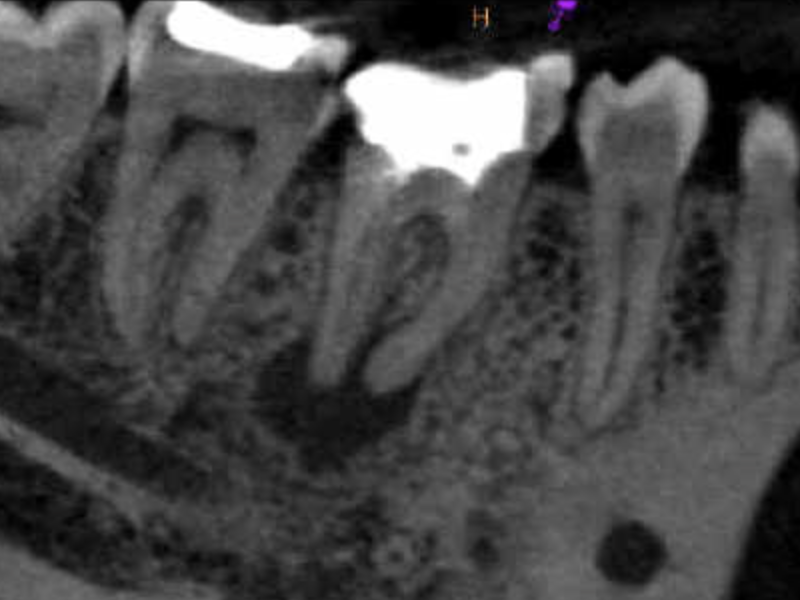

Molar superior anatomía compleja